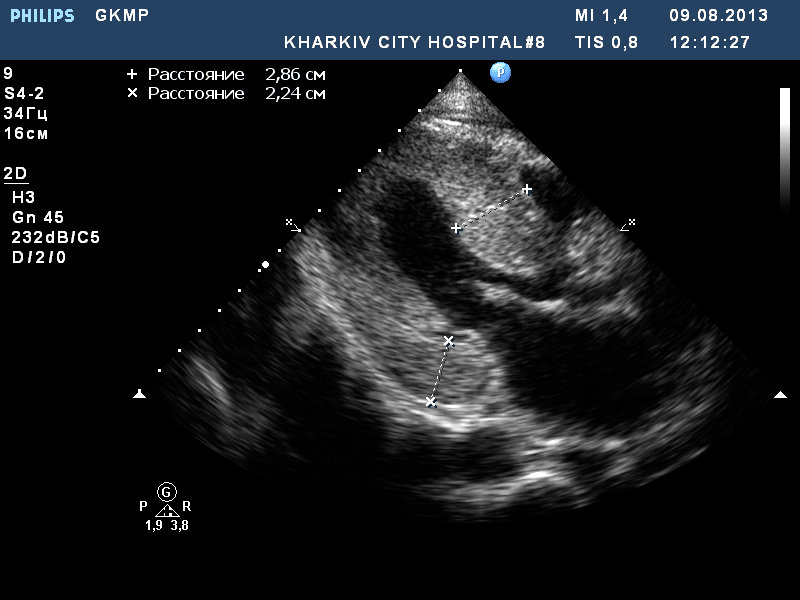

ГКМП. обструкции кровотока в выносящем тракте левого желудочка нет.